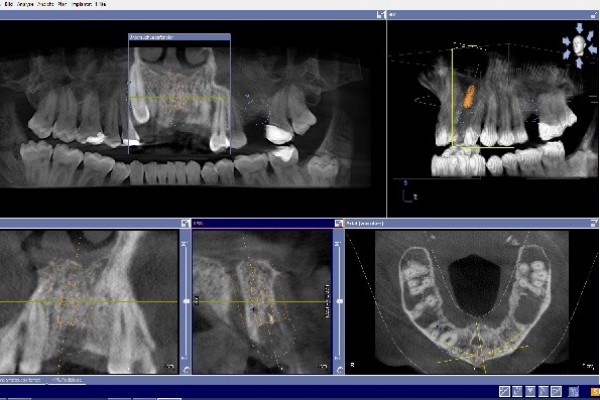

Mit der Digitalen Volumentomographie (DVT) bieten wir unseren Patienten ein hochmodernes dreidimensionales Diagnoseverfahren, welches eine deutlich besseren Bildqualität, erhöhte Sicherheit für Patient und Behandler sowie eine geringere Strahlendosis als bei einer herkömmlichen CT bedeutet .

Die DVT arbeitet mit Röntgenstrahlen. Wie auch die Computertomographie (CT) können mit der DVT hochauflösende Schnittbilder erstellt werden, diese haben jedoch eine deutlich bessere Auflösung. Hierdurch ist eine noch genauere Diagnose und spätere Therapie möglich.

Die Röntgenröhre produziert zweidimensionale Einzelaufnahmen, die von einem Hochleistungsrechner zu einem dreidimensionalen Datensatz umgerechnet werden.

Innerhalb kürzester Zeit wird so direkt eine präzise Diagnosegrundlage erstellt, der wir alle Informationen entnehmen können, die wir für Ihre Therapieplanung benötigen.

• Implantatplanung in der 3D Simulation

• exakte Positionierung von Implantaten

• Einschätzung des Knochenangebots und der Knochenbeschaffenheit vor der Implantatversorgung